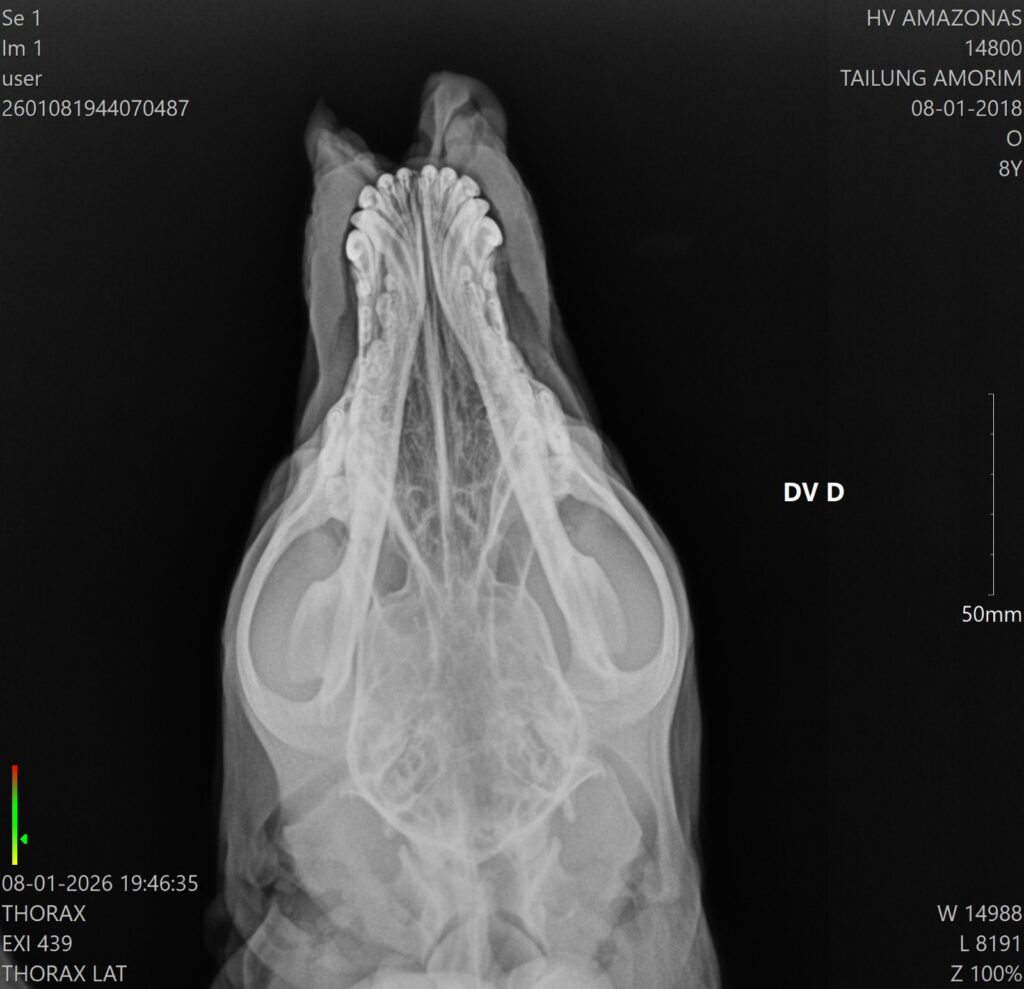

O animal apresentava uma lesão profunda na região do focinho, que foi partido ao meio

De acordo com a equipe hospitalar, o cachorro apresentava uma lesão profunda na região do focinho, mas estava consciente e respondeu bem ao atendimento. A cirurgia foi bem-sucedida e o animal já foi encaminhado para casa, onde permanecerá em observação pelo tutor, além de seguir acompanhado pela equipe multidisciplinar do HPVet-AM.